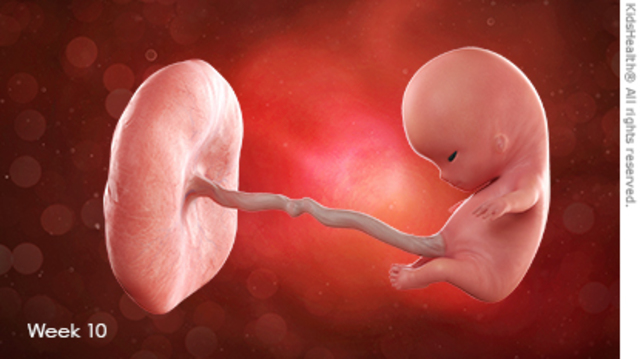

• SEMANA 10

SEMANA 10

Mide entre 28 y 29 mm y pesa casi 5 gramos, comienza la formación de codos y rodillas. Esta semana es la última que se le llamará embrión, después pasará a ser feto. Ya se encuentra totalmente formado, ahora solo falta la maduración.